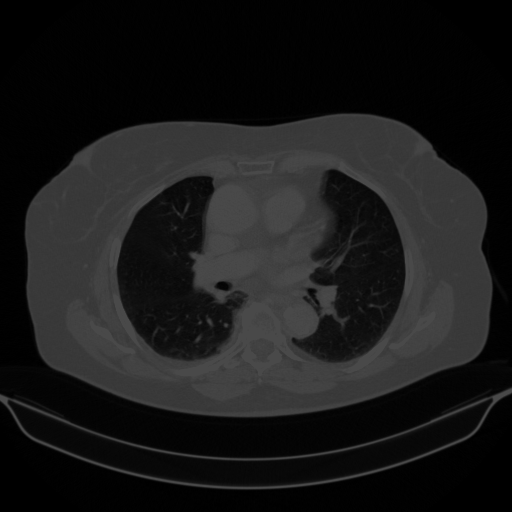

Original VENOUS CT scan

No window - Raw intensity values

Lung window (WL -600, WW 1500 β†’ Low βˆ’1350, High +150)

Mediastinum window (WL 40, WW 400 β†’ Low βˆ’160, High +240)